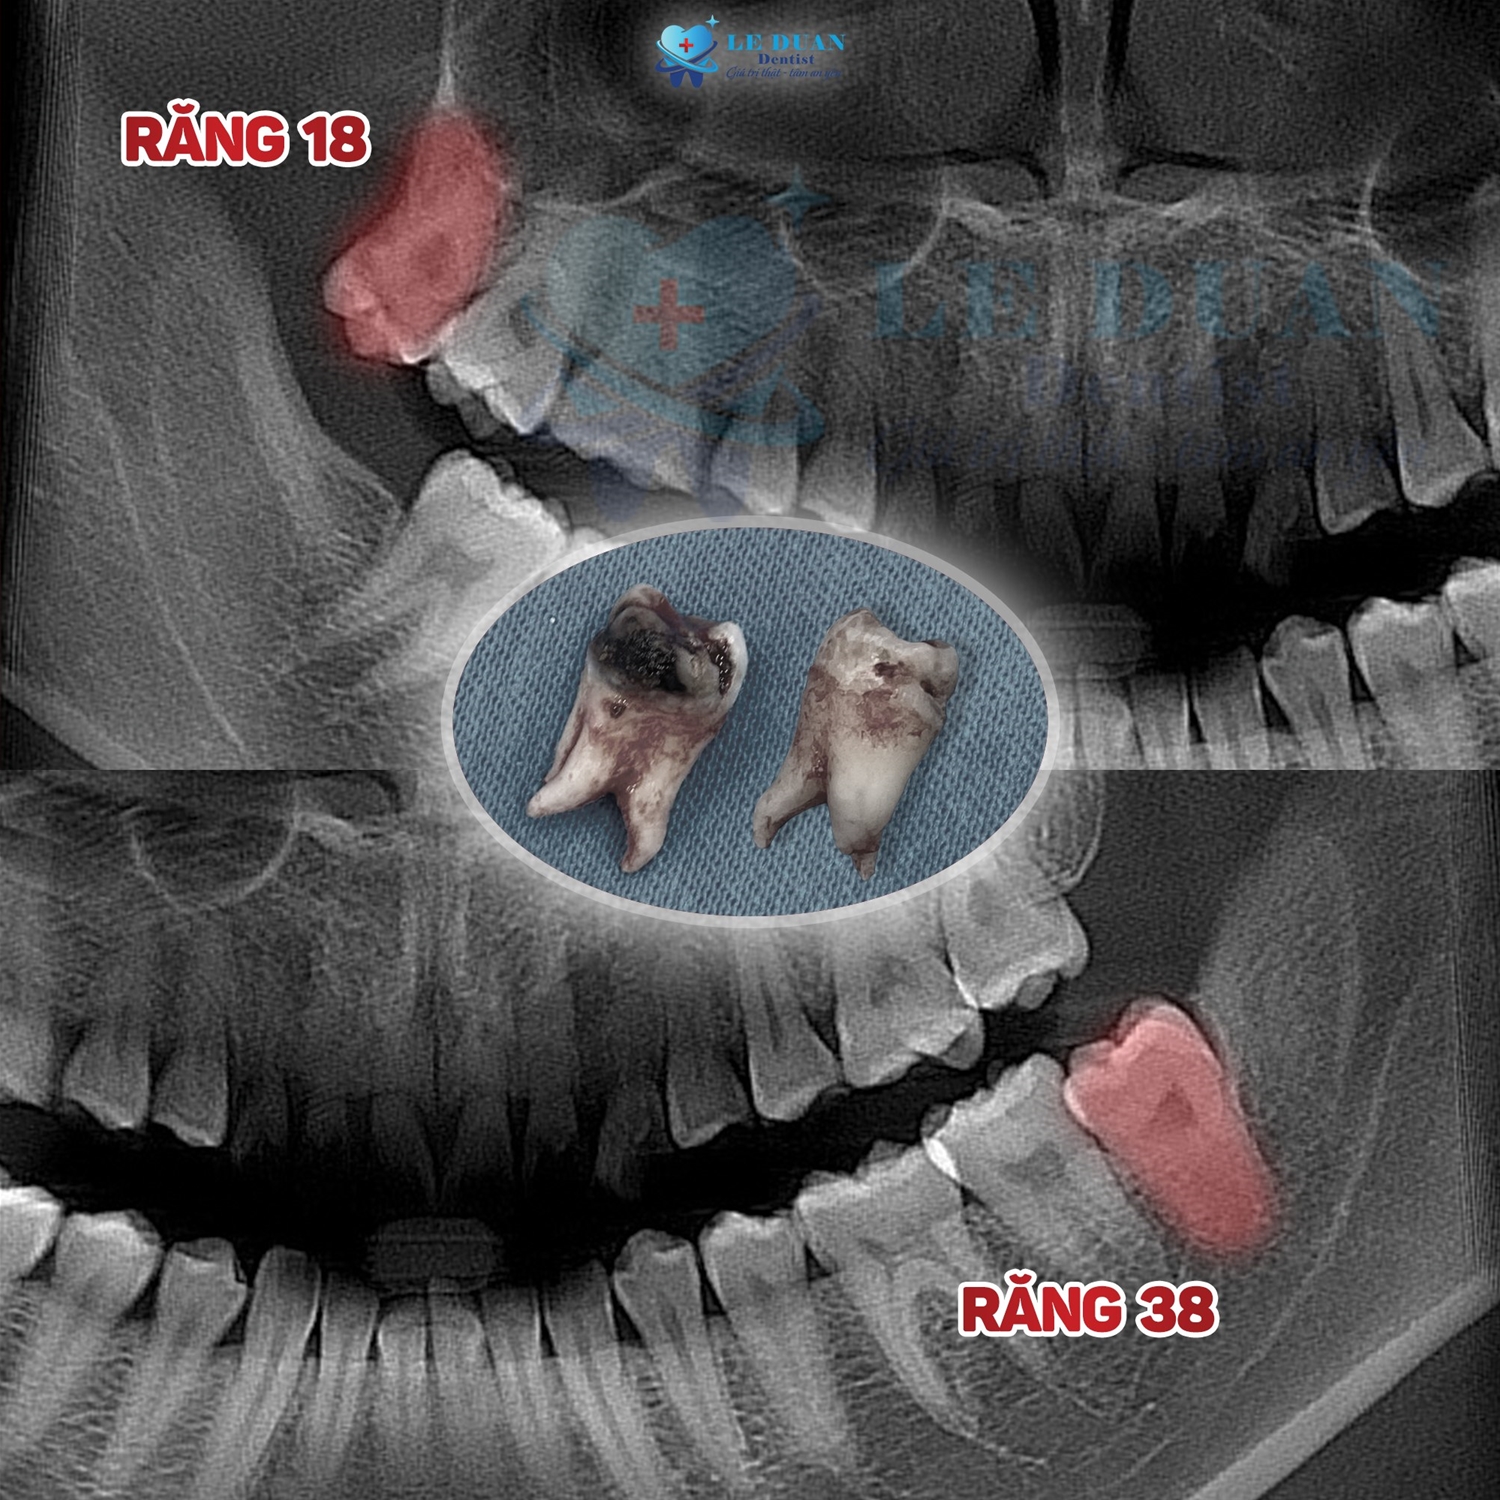

Khám và chụp phim 3D Cone Beam CT: Đây là yếu tố quan trọng nhất để:

Xác định chính xác vị trí răng khôn, độ nghiêng và hình thái chân răng.

Đánh giá mối quan hệ với các cấu trúc quan trọng lân cận như dây thần kinh hàm dưới và mạch máu, giúp tránh các biến chứng như tê bì kéo dài.

Từ đó, bác sĩ có thể tiên lượng cách phẫu thuật tối ưu và chủ động dự phòng các biến chứng có thể xảy ra.

Sử dụng CT Cone Beam để chẩn đoán chính xác